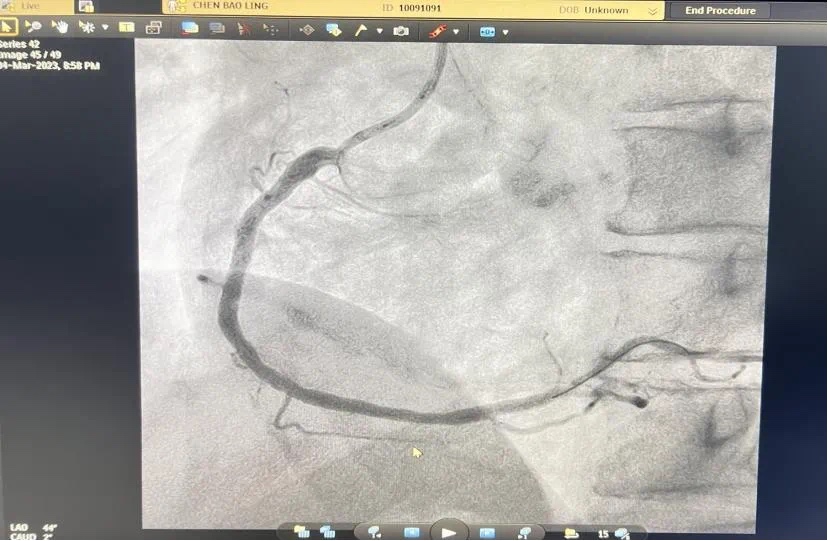

3月4号晚,总医院一个不平凡之夜。19点44分,急诊科汪小卫医生在胸痛中心微信群发送了一条信息:患者程某心电图检查结果。心内科副主任何涛马上回复:患者确诊为急性下壁ST段抬高型心肌梗塞并一键启动导管室,医生熊俊锋、导管室张梅梅立即奔赴导管室穿好铅衣备好急救药品物品,打开除颤仪做好手术准备。19点54分,激活导管室。20点08分患者被送入导管室快速实施冠脉造影,显示患者右冠近段粥样硬化伴“瘤样扩张”,中段发生完全闭塞。结合心电图考虑堵塞血管为右冠,于20点27分成功开通堵塞血管。患者从医院大门到开通血管仅50分钟,大大缩短心肌获得灌注时间,心功能基本不受影响。 术中险象环生,患者心率进行性下降,血压反复异常,经医护人员的及时救治,患者转危为安被安全护送回病房。术前、术后图片如下